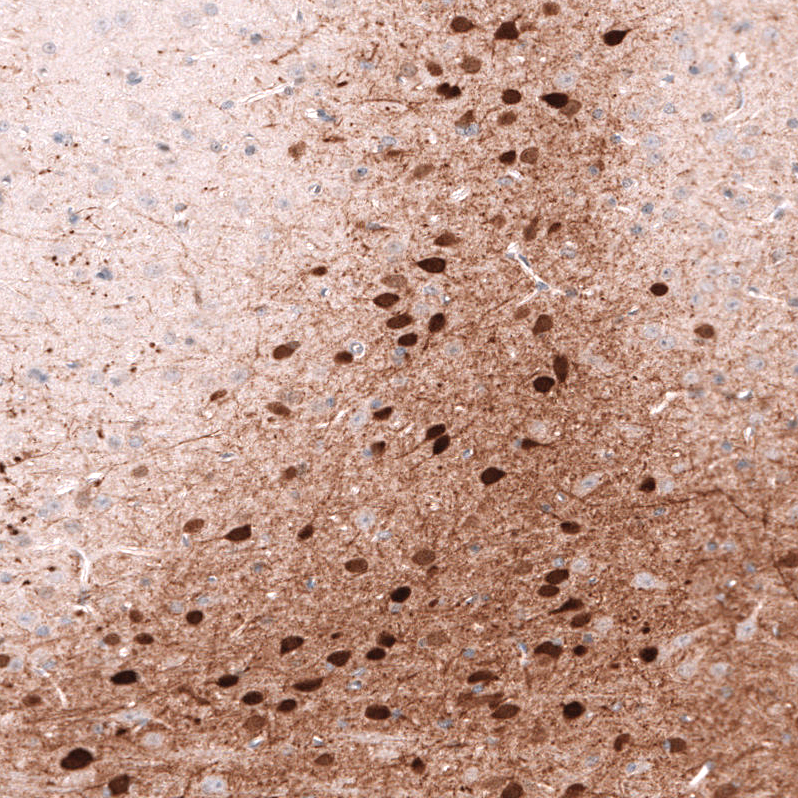

Immunohistochemistry analysis in human cerebral cortex and liver tissues using AMAb91813 antibody. Corresponding CALB2 RNA-seq data are presented for the same tissues.